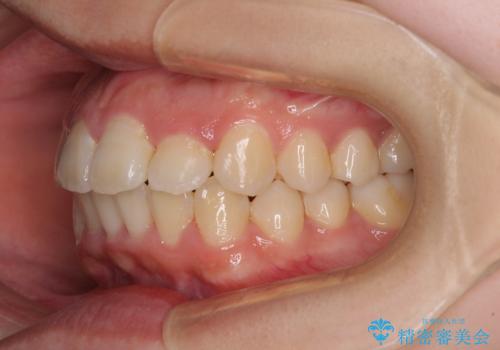

- 上下のデコボコと前歯のクロスバイトを改善したいとのことで来院された患者様です。

極力短期間で治療したいとのことで、ワイヤー装置による矯正治療を行うこととしました。

マウスピースによる矯正治療も提案しましたが、ご自身でのマウスピースの管理の面倒くささと、なるべく早く治療を終えたいとのことで、ワイヤー矯正を選択されました。